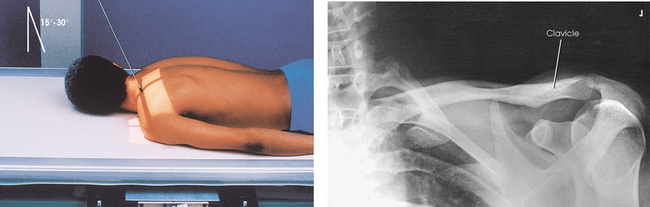

• Have the patient lean backward in a position of extreme lordosis, and rest the neck and shoulder against the vertical grid device. The neck is in extreme flexion (Figs. 5-63 and 5-64).

• Center the clavicle to the center of the IR (see Fig. 5-64).

• Cephalic central ray angulation can vary from the long axis of the torso; thinner patients require more angulation to project the clavicle off the scapula and ribs

• For the standing lordotic position, 0 to 15 degrees is recommended (see Fig. 5-63).

• For the supine position, 15 to 30 degrees is recommended (see Fig. 5-64).